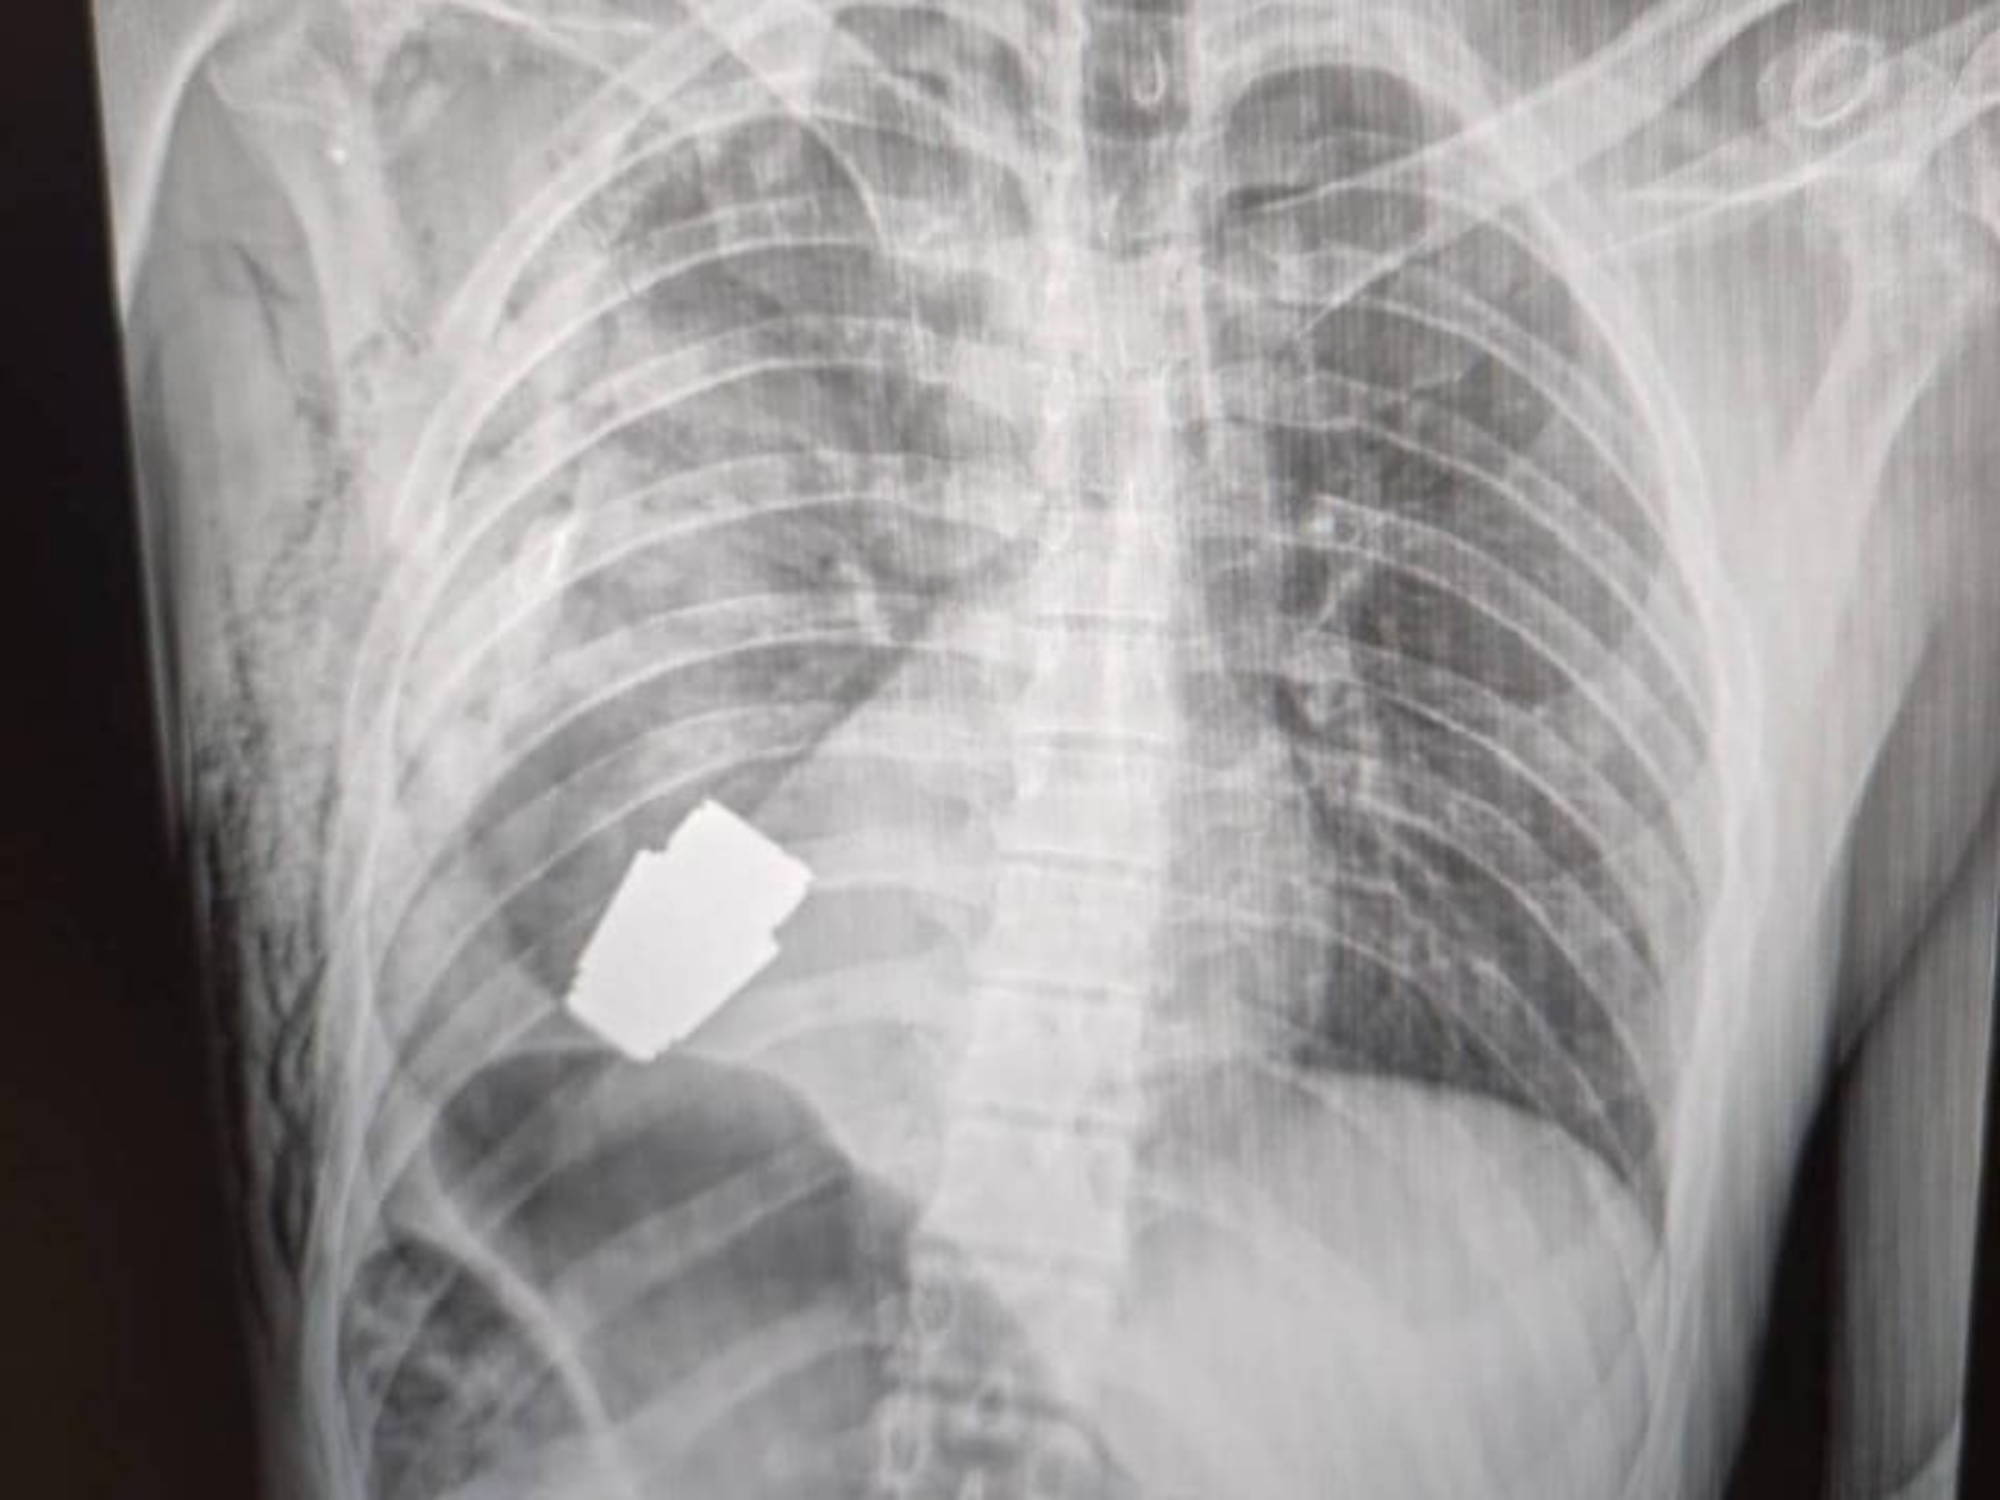

Ein schockierendes Röntgen-Foto: Eine scharfe Granate steckt in der Brust eines ukrainischen Soldaten.

Das Geschoss sei, abgefeuert durch einen Granatenwerfer, in die Brust des Soldaten eingedrungen und unterhalb seines Herzens stecken geblieben, dort allerdings nicht explodiert. Bei der Granate habe es sich laut Angaben um eine VOG-Granate gehandelt – 40-Millimeter-Splittermunition, die etwa 275 Gramm wiegt.